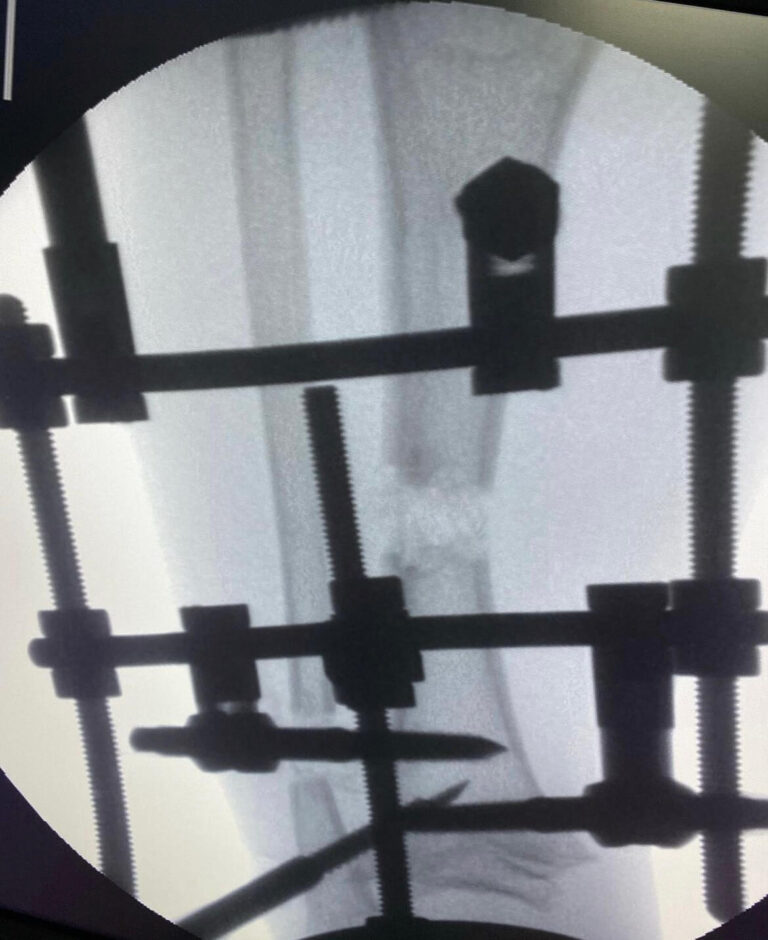

Современная сложная реконструктивная ортопедия в

мц «ЛАДИСТЕН КЛИНИК» город Киев Украина

- Малоинвазивные хирургические методы, позволяющие минимально вмешиваться в организм пациента и гарантируют эффективное лечение и легкую адаптацию.